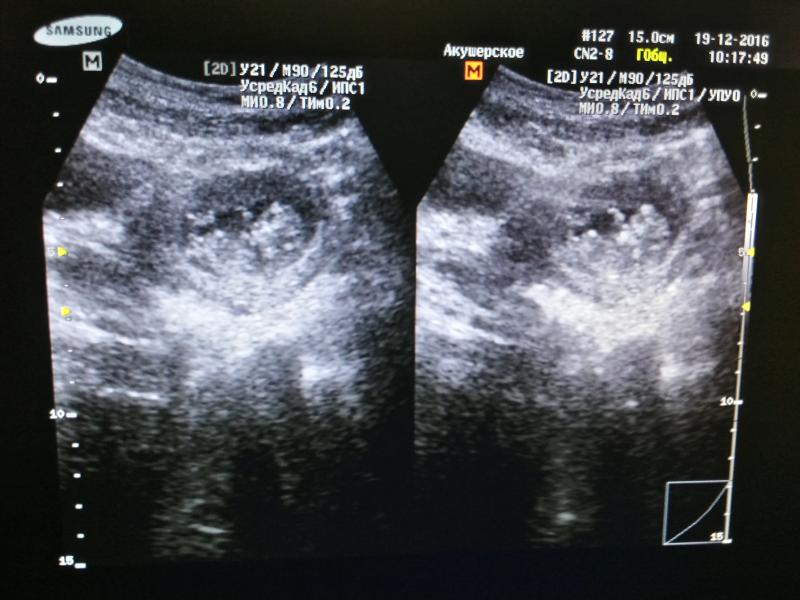

#первоефото моей малышки 💝 Пока не знаем пол, но кто бы там ни был ждем тебя с нетерпением 😊😘😘😘 (фото 9нед.)